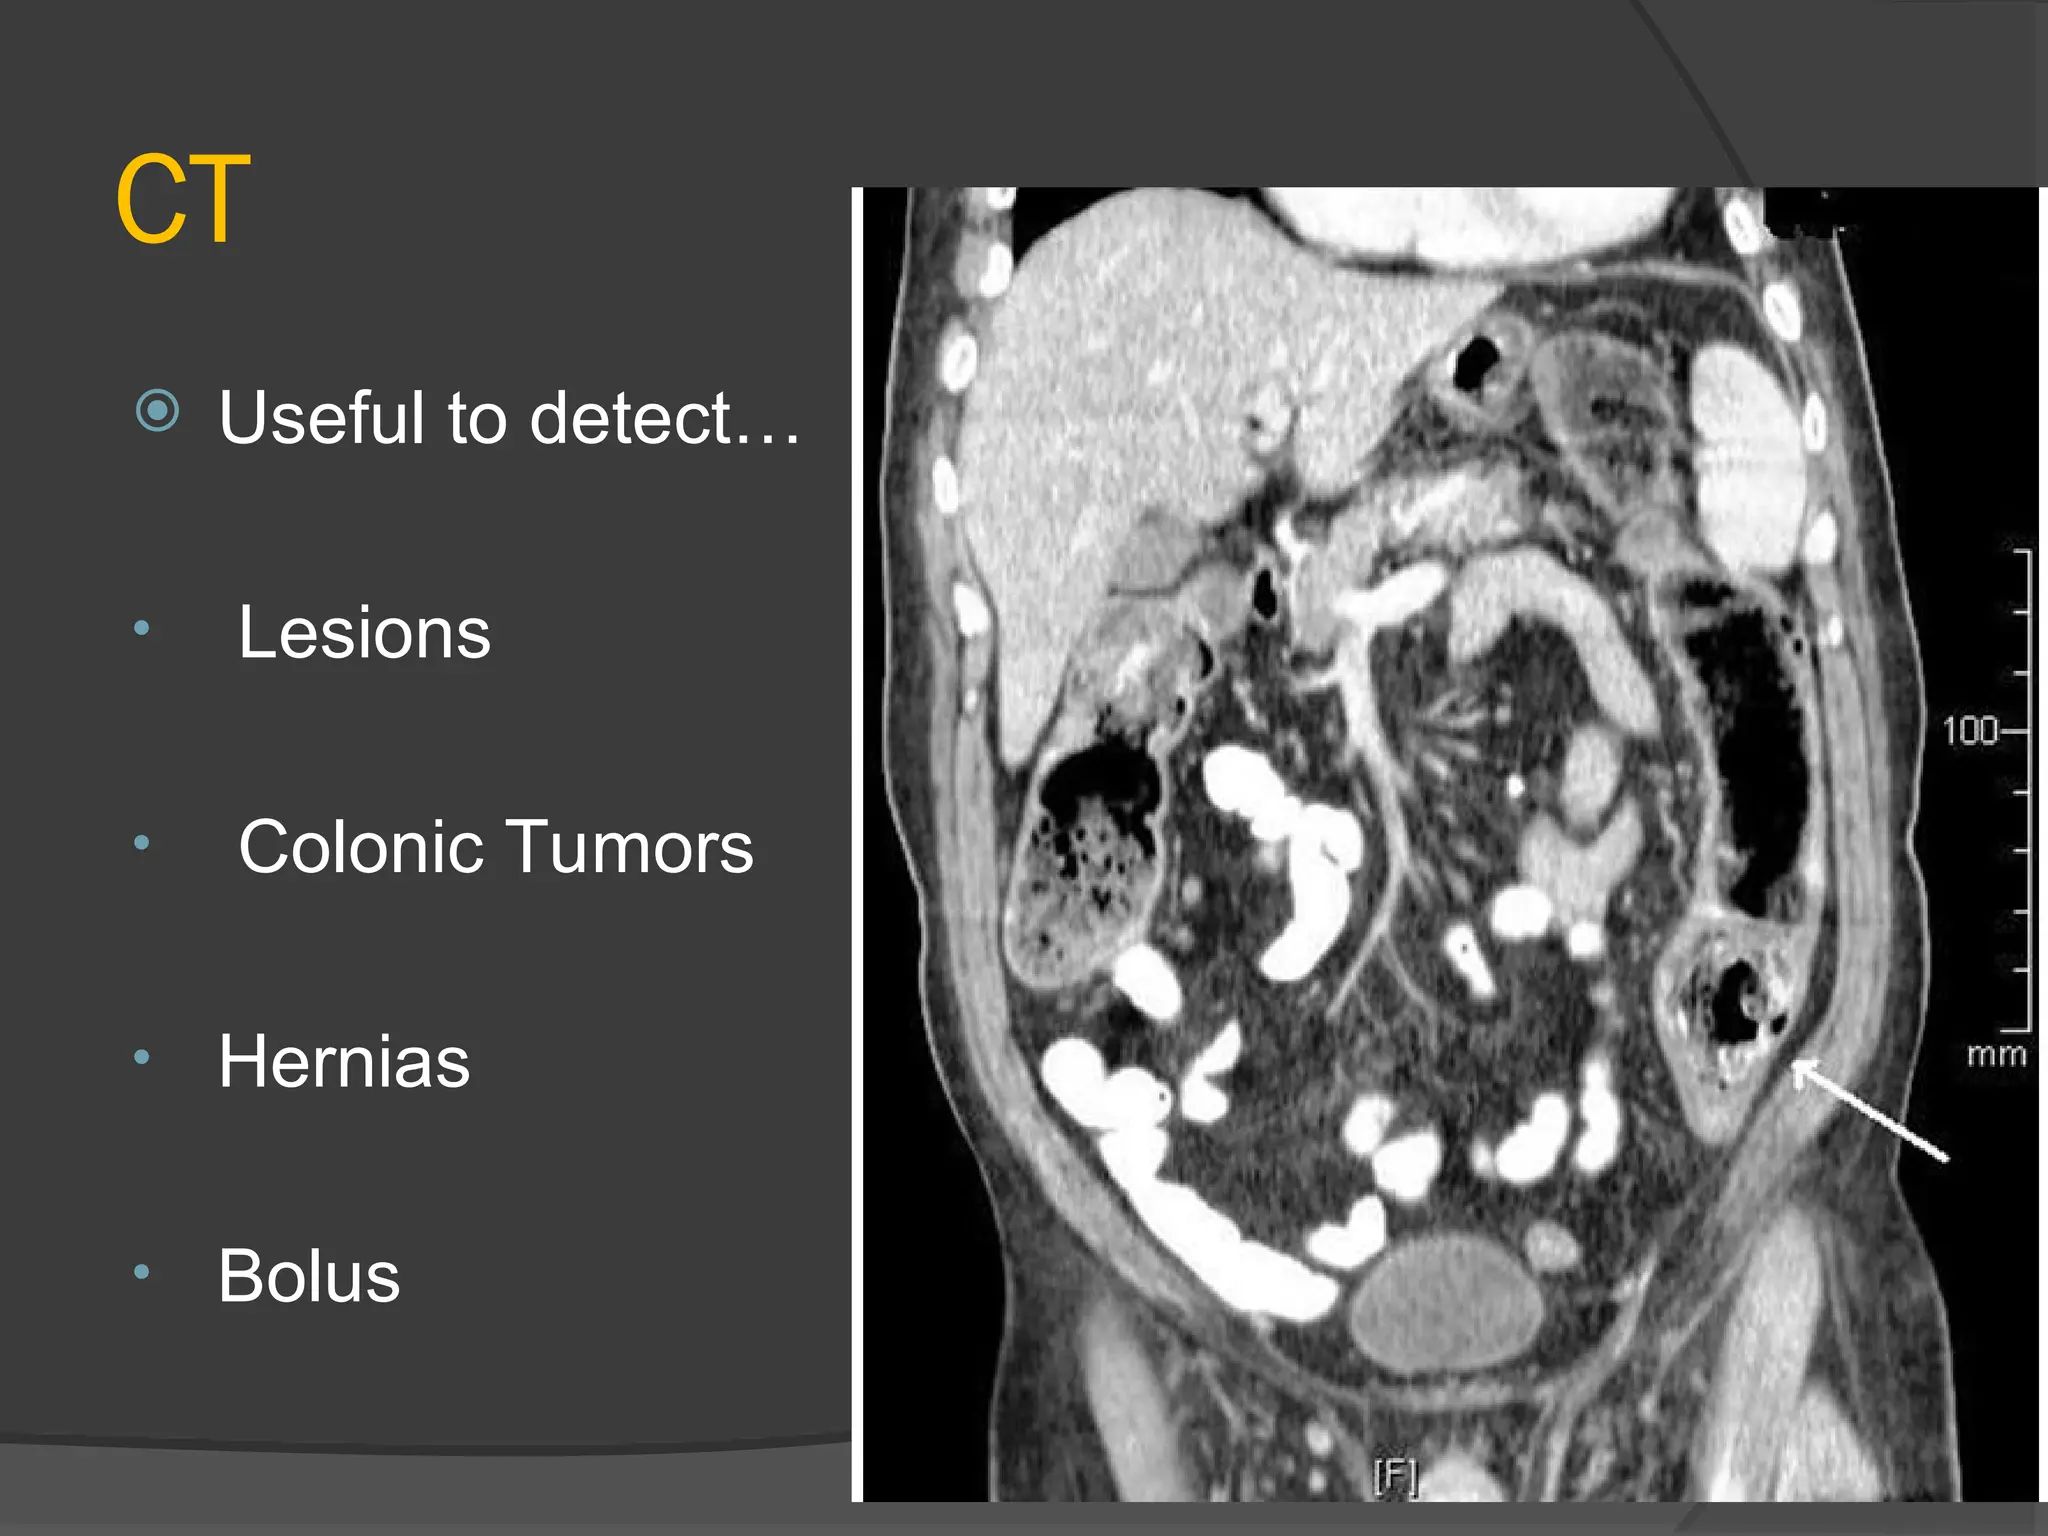

CT

 Useful to detect…

• Lesions

• Colonic Tumors

• Hernias

• Bolus

CT  Useful todetect… • Lesions • Colonic Tumors • Hernias • Bolus